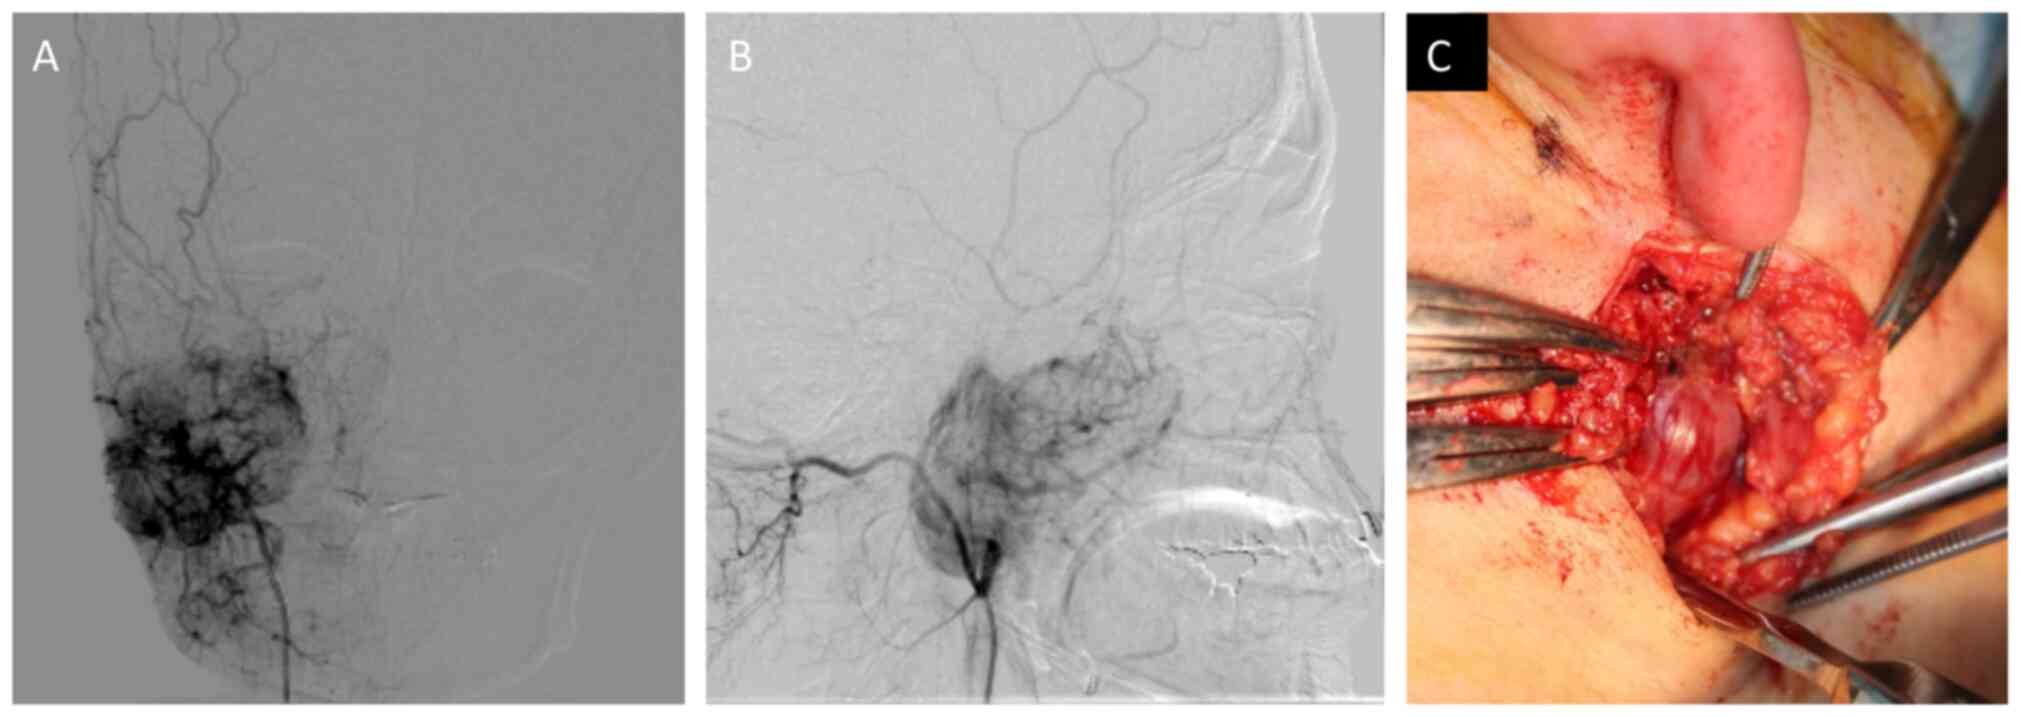

An open biopsy was performed on the lower part of the right auricula following angiography assisted vascular embolization of the maxillary artery (Fig. 4A and B). The tumor was found in deeper layers than the parotid gland, and bleeding was not observed during biopsy due to the effect of vascular embolization (Fig. 4C). Immunohistologically, CD99 was positive, CD34 was positive only for vascular endothelium, and B cell lymphoma 2 (Bcl-2) was weakly positive. These findings suggested SFT. Then, athological diagnosis was confirmed as SFT (Fig. 5A-H).

Figure 4.

(A) Frontal view of angiography, (B) Side view of angiography, (C) intra-operating view of open biopsy.